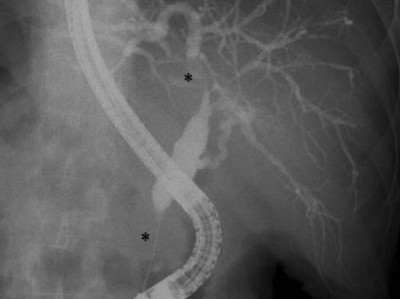

Schmerzloser Ikterus und Sicca-Symptomatik: Ihre Diagnose?

Ein 53-jähriger Patient stellte sich mit schmerzlosem Ikterus, Nachtschweiß und ungewolltem Gewichtsverlust von etwa 8 kg vor. Darüber hinaus beklagte der Patient eine ausgeprägte Sicca-Symptomatik. Letztlich kamen die Ärzte zwei zusammenhängenden Erkrankungen im Sinne eines Überlappungssyndroms auf die Spur.

Sialendoskopie/© UKL-HNO, Otoskopie bei einem jungen Kind/© SolStock / Getty Images / iStock (Symbolbild mit Fotomodellen), Speicheldrüsensonographie der Glandula parotis links bei Sjögren-Syndrom/© Zehrfeld N. et al. / all rights reserved Springer Medizin Verlag GmbH, Peritonsillarabszess links/© Matti Sievert et al. / all rights reserved Springer Medizin Verlag GmbH, Lymphknoten mit follikulärem Lymphom/© Meng S / all rights reserved Springer Medizin Verlag GmbH, Drehen einer Marihuanazigarette/© guruXOX / stock.adobe.com, IMRT-Bestrahlungsplan eines Ösophaguskarzinoms/© Rühle, A., Huber, P.E. / all rights reserved Springer Medizin Verlag GmbH, Masern, Mumps, Röteln im Impfpass/© Astrid Gast / stock.adobe.com, Aufziehen von Flüssigkeit mit Spritze/© Eisenhans / Fotolia, Skalpell/© imago, Histopathologisches Präparat/© K. Mantsopoulos et al. / all rights reserved Springer Medizin Verlag GmbH, Ultraschallbild der linken Glandula submandibularis/© V. Volgger, Doppelstenose des Ductus hepatocholedochus/© Springer Medizin, Search Icon, Infusion/© georgeoprea9 / Getty Images / iStock, Frau wird Blut abgenommen/© andresr / Getty Images / iStock (Symbolbild mit Fotomodellen), Junge Ärztin vor einem Triage-Zelt/© Milos / Stock.adobe.com (Symbolbild mit Fotomodell)